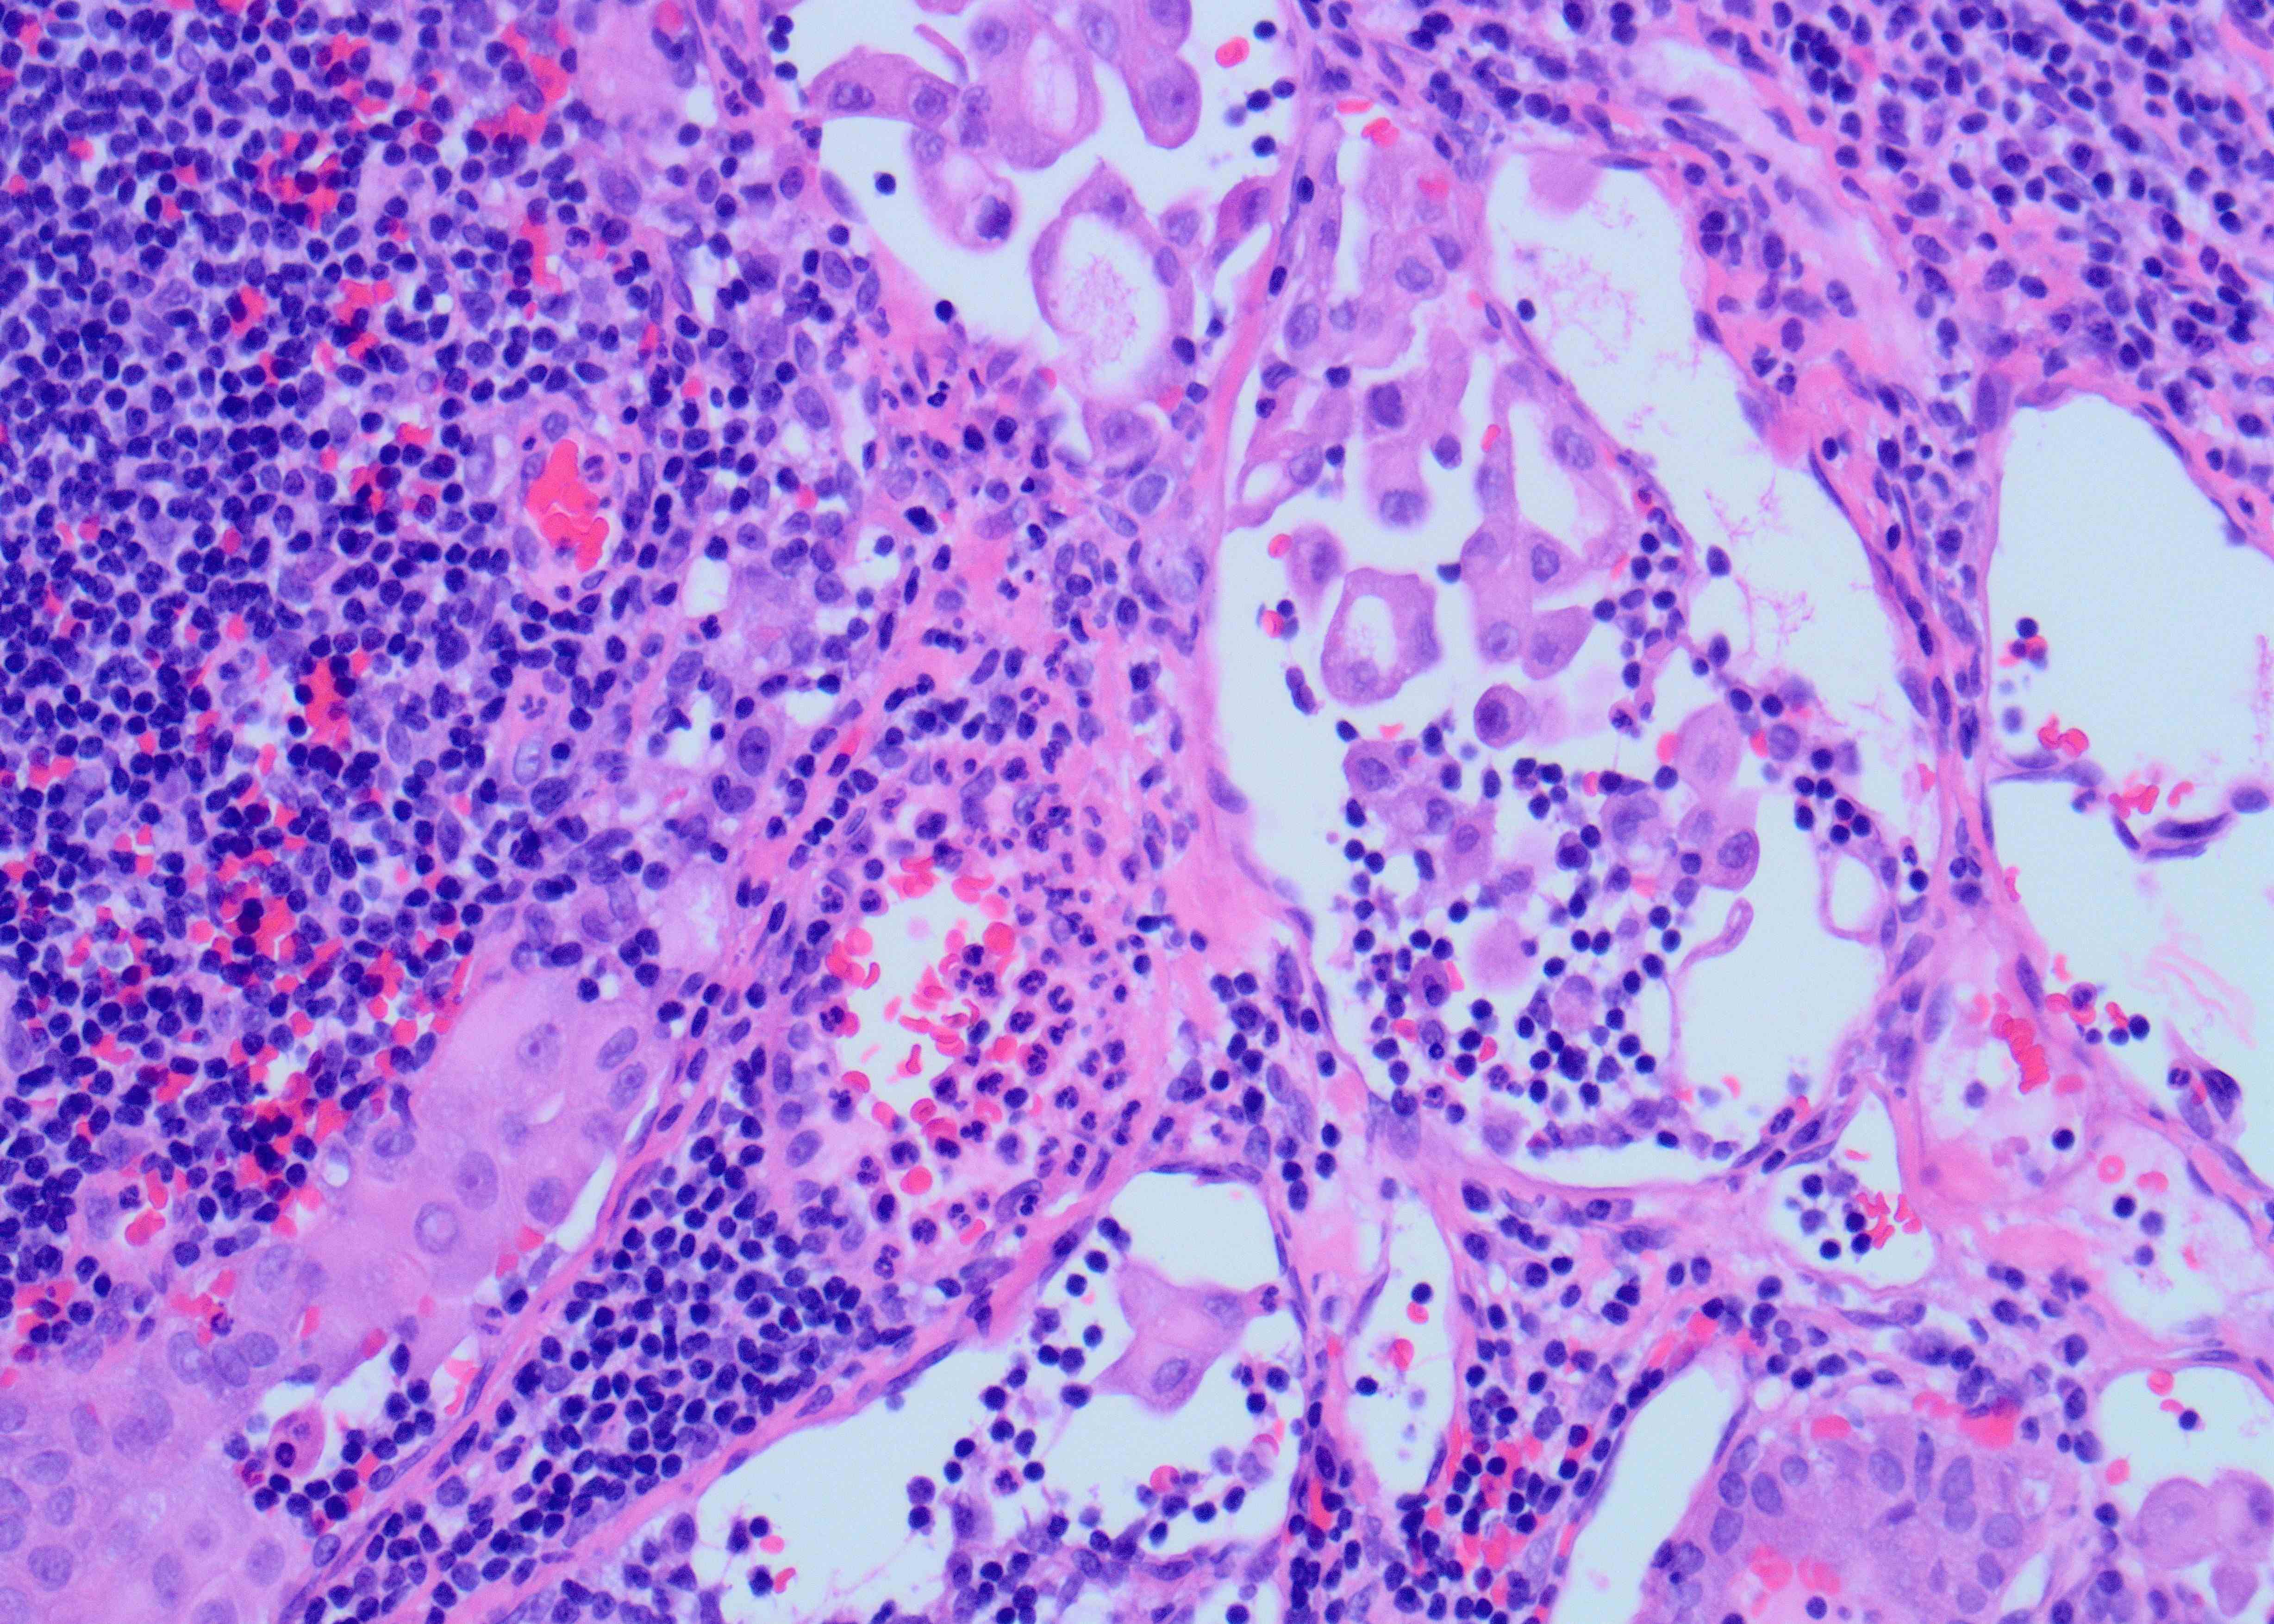

Although the specimen source was described as a neck mass, the presence of scattered lymphocytes in the back ground is suggestive of a lymph node aspirate. In addition, there are scattered clusters of large epithelioid cells but with relatively low nuclear to cytoplasmic ratio due to moderate amount of cytoplasm showing tapered cytoplasmic tails (Figure A). The high power shows a syncytial aggregate of atypical cells (Figure B). These cells have moderately abundant amount of granular cytoplasm with distinct margins. Occasional cells have tall cell morphology, evident predominantly along the periphery of the cluster as well as a single cell with soap bubble like intranuclear pseudoinclusion (arrow). The cytomorphology is identical to the metastatic cells present in the previously excised cervical lymph node (Figure C). All these features favor tall cell variant of papillary thyroid carcinoma (PTC), metastatic possibly to a cervical lymph node. Histopathologic feature of primary PTC, tall cell variant, is shown in Figure D.

PTC is the most common malignancy of the thyroid gland and has overall a favorable prognosis, with few exceptions like PTC, tall cell variant. This variant of PTC is often associated with more aggressive behavior with a higher risk of recurrence than classic PTC. Therefore, a preoperative diagnosis of tall cell variant or even noting the tall cell features on FNA may help in triaging for appropriate patient management. The most helpful cytologic diagnostic features include increased numbers of tall tumor cells arranged as single cells and at the periphery of cellular groups containing granular cytoplasm and distinct cell borders, cytoplasmic tails, and cytoplasmic cuffs (peripheral rimming of cytoplasm in cellular groups). Intranuclear “soap-bubble” pseudoinclusion is not readily identifiable but when present is specific for tall cell variant/ changes.